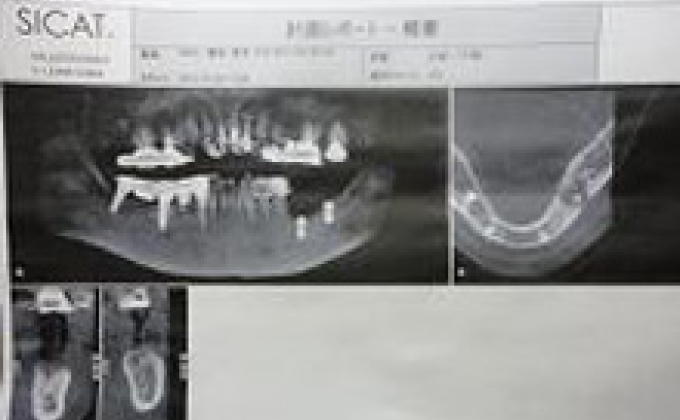

1. 安全・確実な手術のためにCT・模型で分析。詳細な手術ガイドを作成

安全・確実な手術のために、CT・模型で分析し、インプラント埋入方向を細かく決定した手術ガイドをつくり、さらに手術前に模型上で試してから本番の手術を行なっています。インプラントレポートを配布しています。

①診断

②ステント

③CT分析